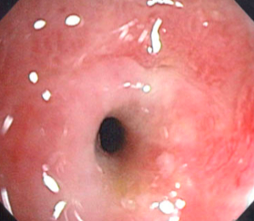

What do you see here?

What’s up with this gastric outlet?

What is one of the ways to relieve gastric obstruction by an un-resectable tumor?